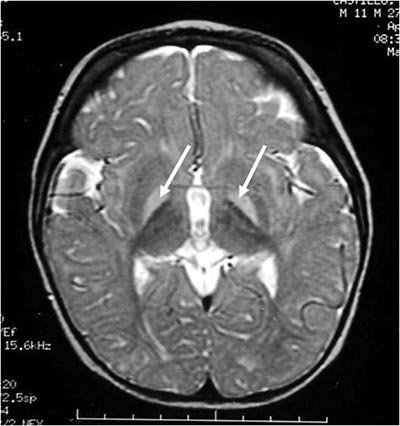

kernicterus brain damage at birth

Also known as bilirubin encephalopathy, kernicterus is a type of neurological damage that commonly affects the brainstem and basal ganglia. These injuries normally result in dyskinetic cerebral palsy symptoms like fluctuating muscle tone, repetitive writhing movements, and speech impairment.

Kernicterus damage is a common cause of cerebral palsy movement disorders and other complications like hearing loss and cognitive impairment.